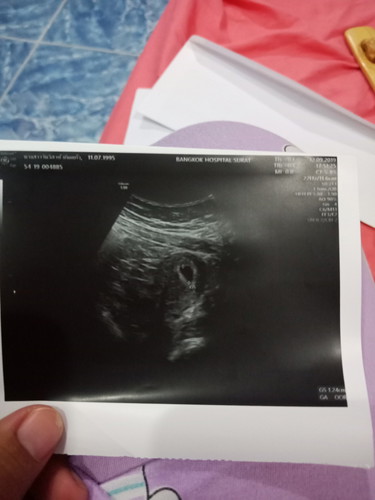

ถ้านับจากปจดได้6wแต่ไข่ตกช้าเรานับเป็น5wแต่วันนี้ไปอัลตราซาวเจอถุงตั้งครรภ์ขนาด1เซ็นยังไม่เจอถุงไข่แดงน่ะค่ะ(ซาวทางหน้าท้องน่ะค่ะ)แต่เครื่องอัลตราซาวไม่บอกอายุครรภ์ค่ะแบบนี้ผิดปกติไหมแล้วเมื่อไรจะเจอถุงไข่แดงแล้วตัวอ่อนหมอนัดอีก3สัปดาห์ค่ะแบบนี้ถือว่ากี่weekได้ค่ะ